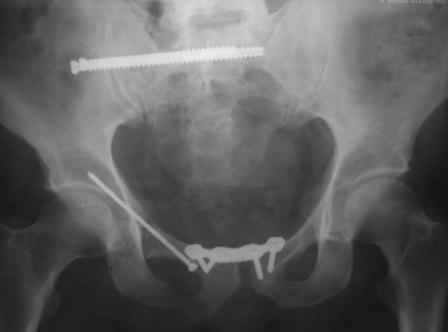

в архиве нашел подобный случай

С Уважением А.Миронов(Новокузнецк)

Уважаемый коллега! Огромное спасибо за рекомендации и иллюстрации! Задний комплекс, а точнее КПС не стал фиксировать т.к. само сочленение и суставная поверхность крестца целое, на кт-срезе имеет место краевой перелом и то не завершенный, учитывая что передняя связка КПС целая (а она сами знаете мошная)не стали фиксировать и клинический пациент не регировал, только КТ. Еще на Ваших фото винты вошли через кортикальный слой или ближе к перелому, а у нас вход в лон получилось прямо с мыса симфиза, т.е. перелом слева, винт зашел справа налево. Или это не принципиально?. С уважением Ерсин Жунусов.